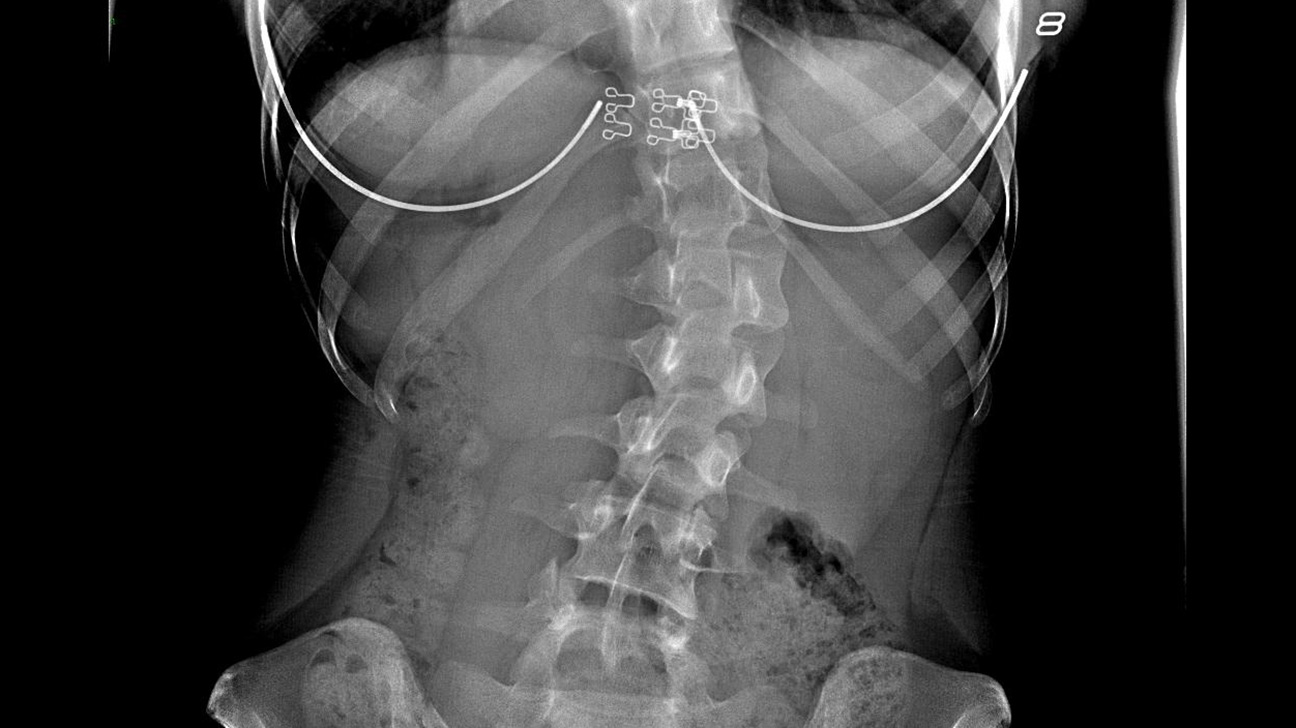

Diagnosis

Your physician conducts a physical exam by observing your back while you stand with your arms at your side. The doctor will check for spinal curvature and symmetry of your shoulder and waist.

your physician might also perform the following imaging tests;

X-ray to show the picture of your spine